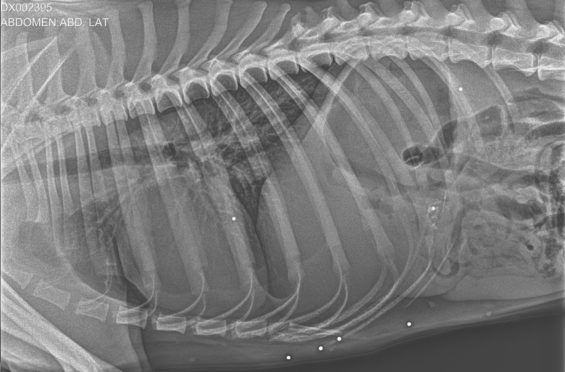

Рентген выжившей собаки из поселка Любимовка, на котором видно дробь Фото: Ольга Ефремова